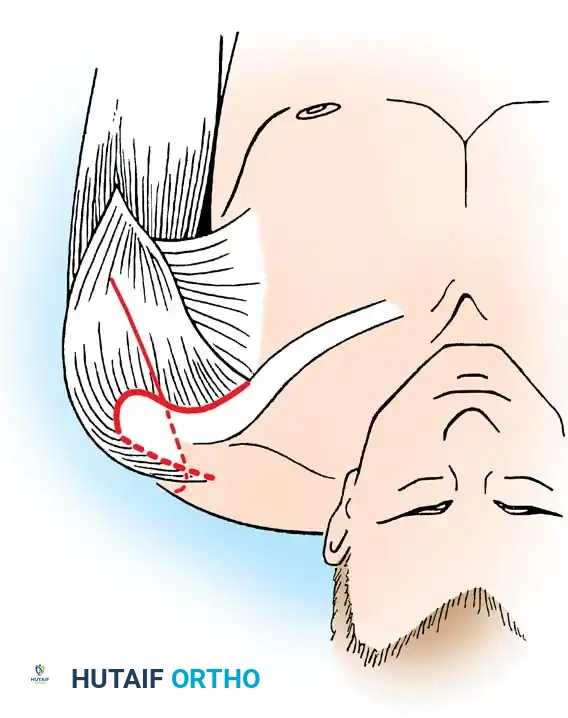

1. Patient Positioning and Incision

The patient is typically placed in a beach-chair position or lateral decubitus position, depending on surgeon preference. The entire forequarter, including the neck, chest, and arm down to the hand, must be prepped and draped free to allow for intraoperative assessment of arm positioning.

A broad strap incision is utilized. The incision begins over the spine of the scapula, extends laterally over the acromion, and curves distally down the anterolateral aspect of the humerus.

2. Surgical Exposure

The deltoid muscle is split or reflected off the anterior and lateral acromion. The underlying rotator cuff tendons (supraspinatus, infraspinatus, and subscapularis) are systematically excised to fully expose the articular surfaces of the humeral head and the glenoid fossa. The undersurface of the acromion is also exposed, as it will serve as a secondary fusion bed.